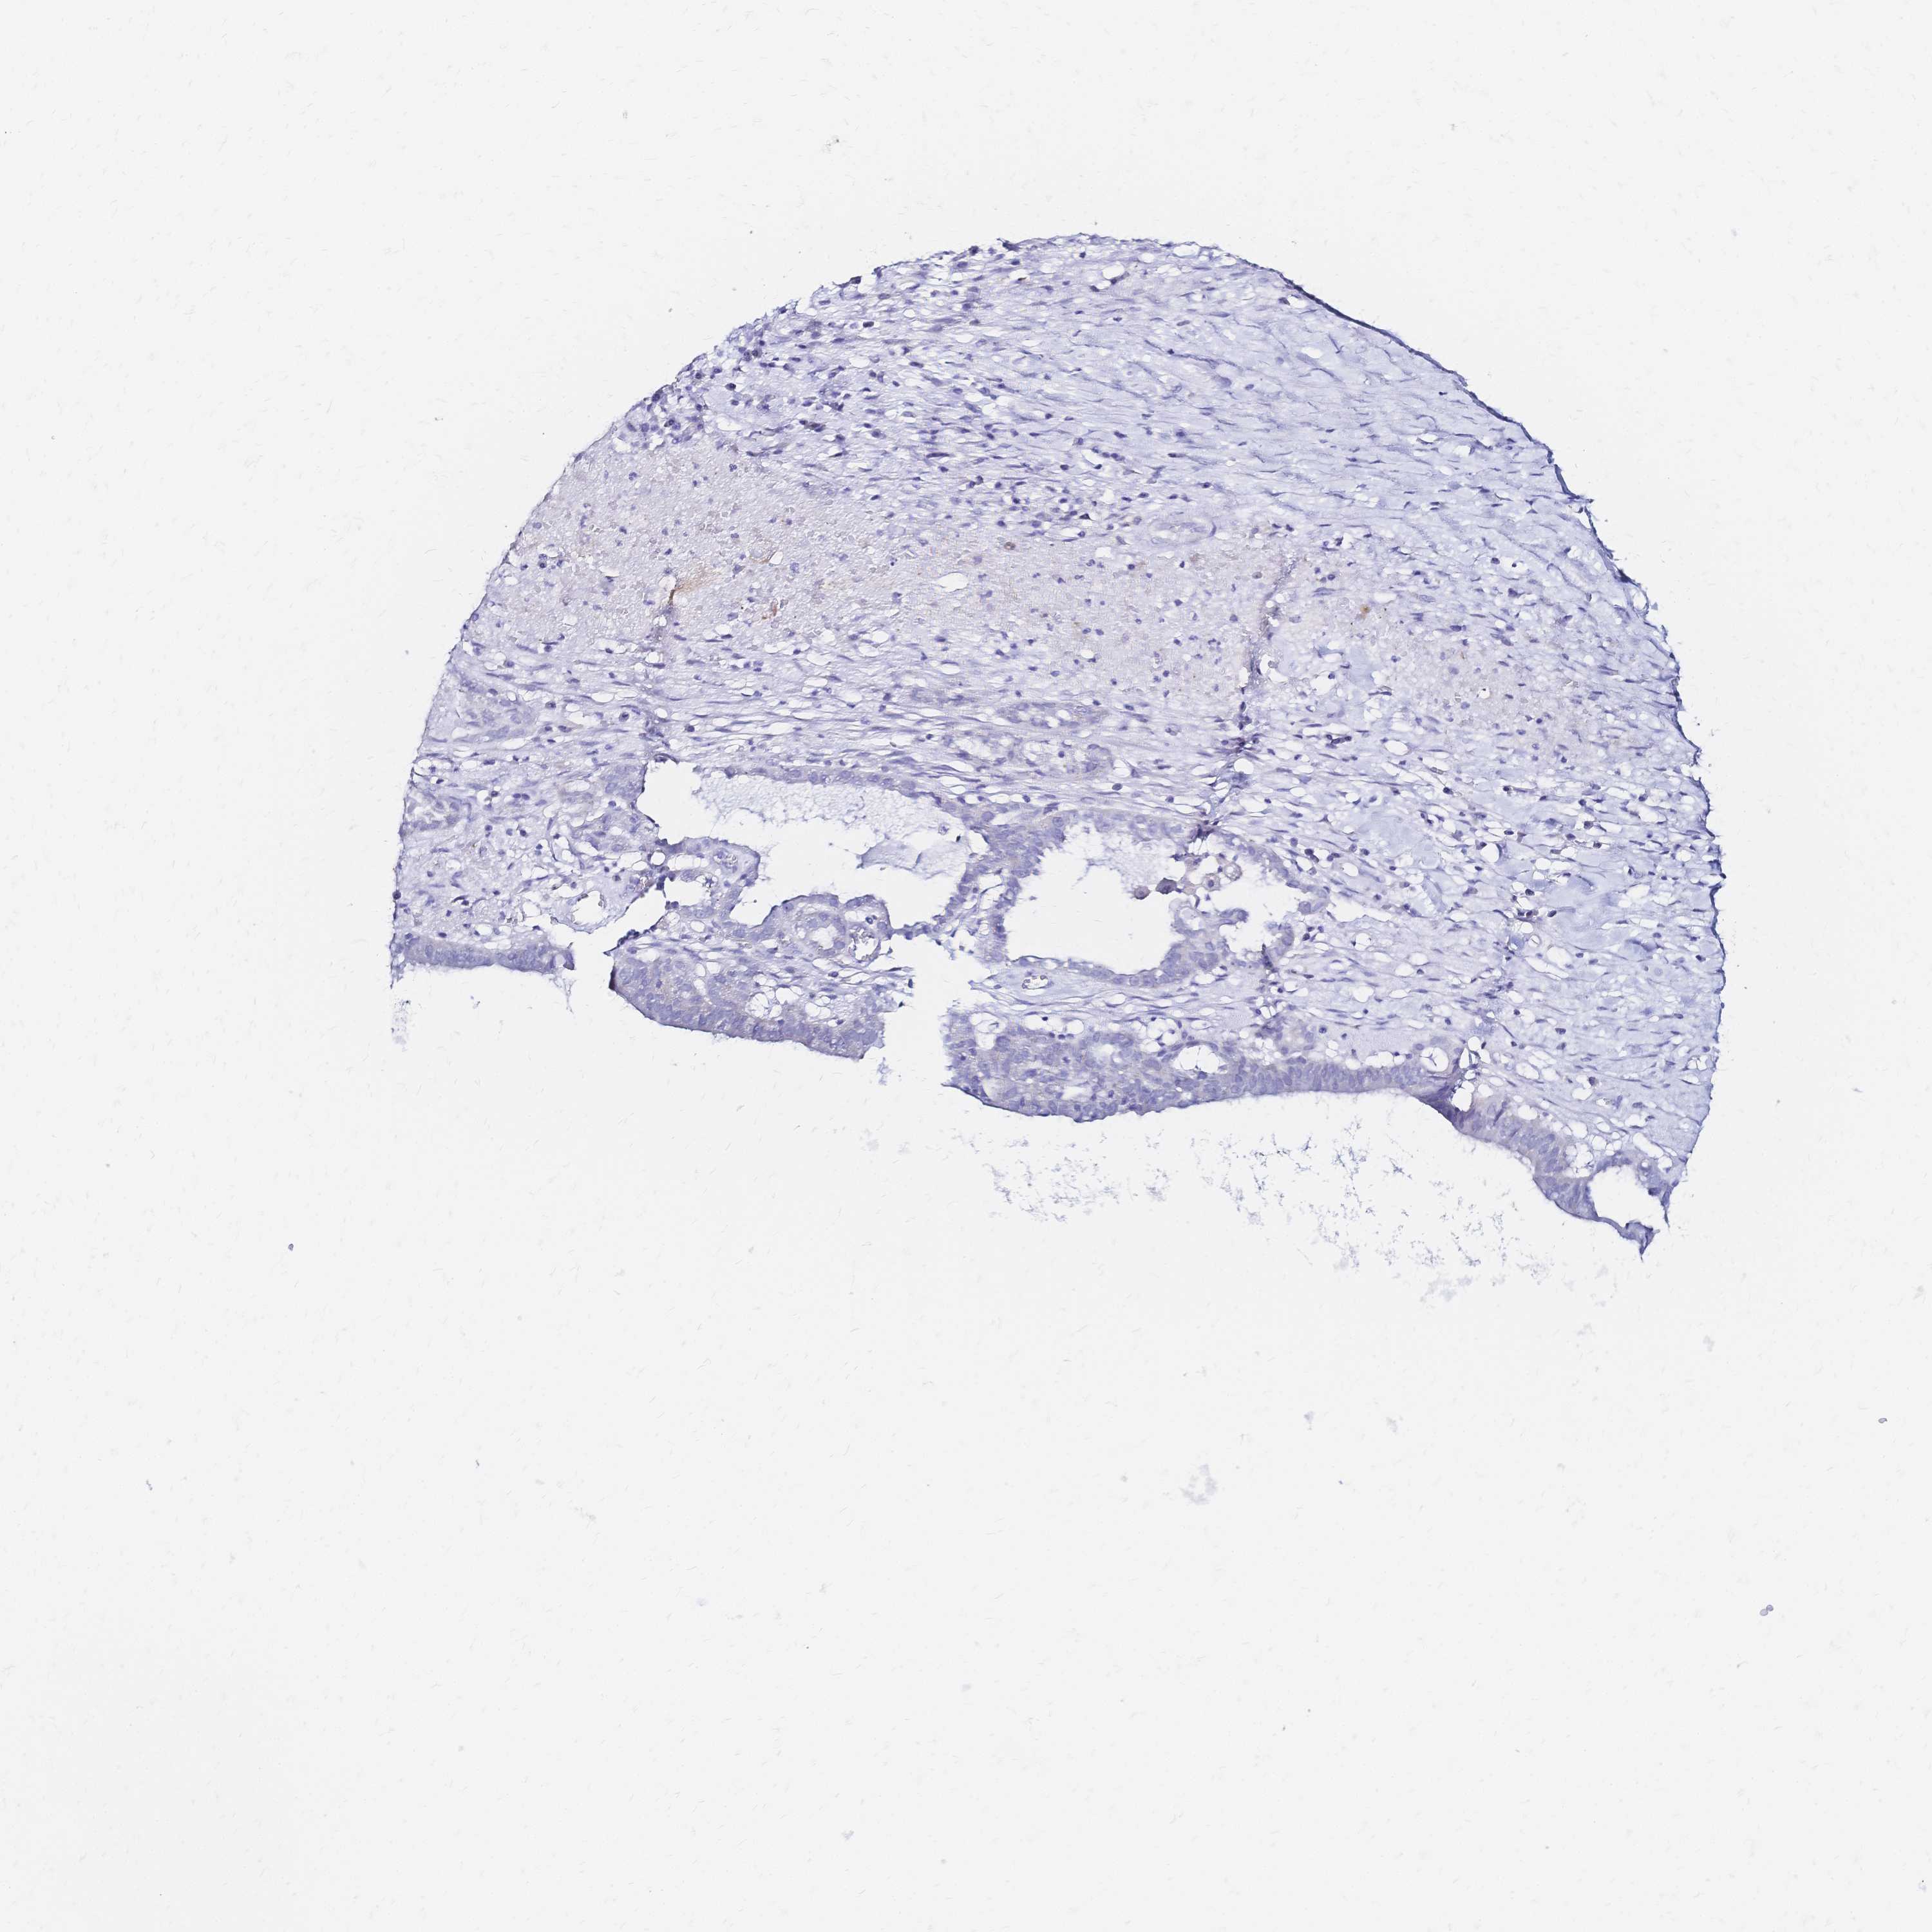

OVARIAN CANCER - Protein expressioni

A mouse-over function shows sample information and annotation data. Click on an image to view it in a full screen mode. Samples can be filtered based on level of antibody staining by selecting one or several of the following categories: high, medium, low and not detected. The assay and annotation is described here.

Note that samples used for immunohistochemistry by the Human Protein Atlas do not correspond to samples in the TCGA dataset.

Antibody stainingi

Antibody staining in the annotated cell types in the current human tissue is reported as not detected, low, medium, or high, based on conventional immunohistochemistry profiling in selected tissues. This score is based on the combination of the staining intensity and fraction of stained cells.

Each image is clickable and will lead to virtual microscopy that enables deeper exploration of all samples and also displays staining intensity scores, fraction scores and subcellular localization as well as patient and tissue information for each sample.

Antibody HPA051805

Antibody HPA055106

Antibody CAB015467

Staining

High

Medium

Low

Not detected

Intensity

Strong

Moderate

Weak

Negative

Quantity

>75%

75%-25%

<25%

None

Location

Nuclear

Cytoplasmic/membranous

Cytoplasmic/membranous,nuclear

Cystadenocarcinoma, serous, NOS

Cystadenocarcinoma, mucinous, NOS

Carcinoma, endometroid